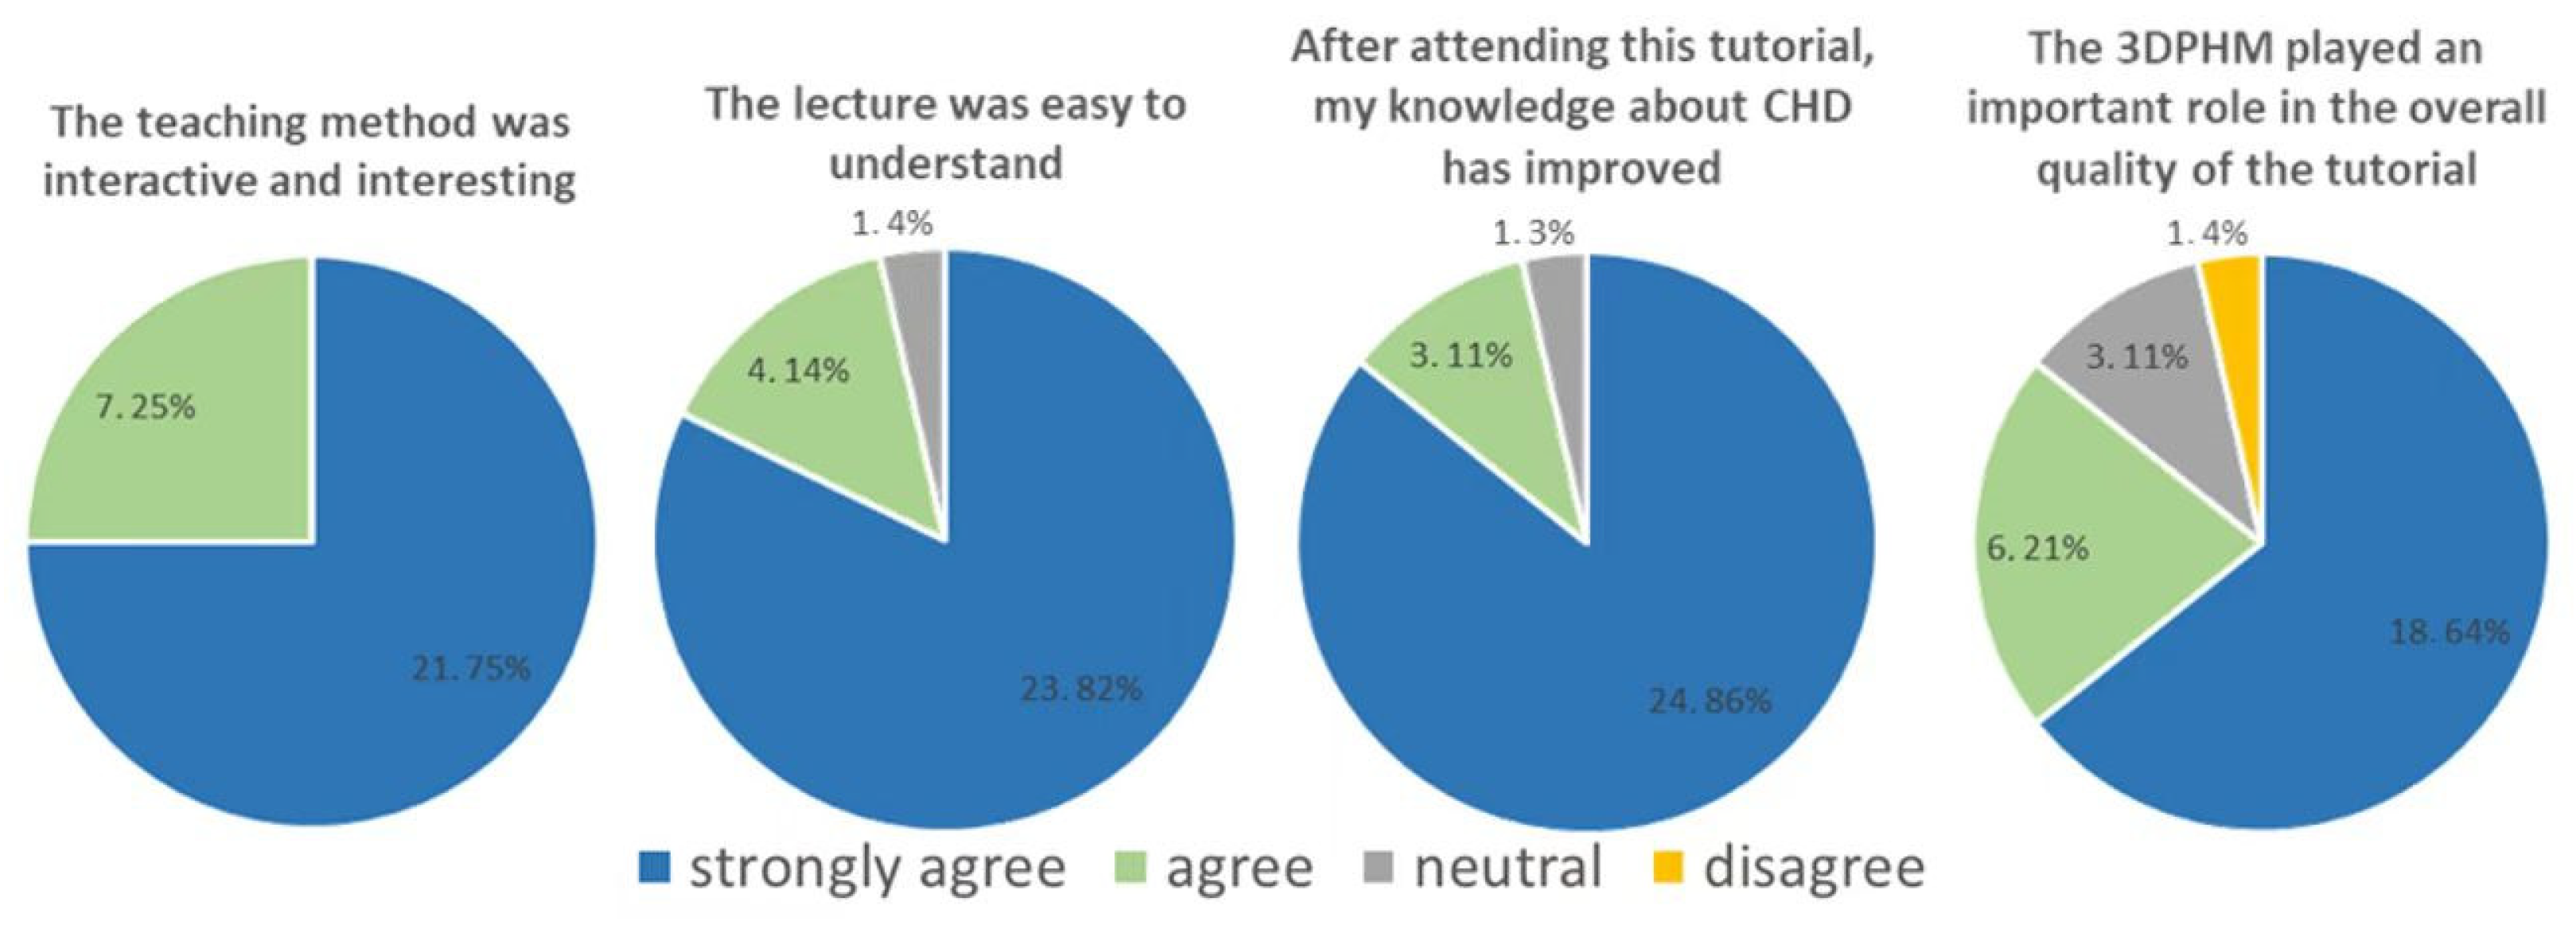

4.2. 3D-Printed CHD Models in Medical Education

- Karsenty, C.; Guitarte, A.; Dulac, Y.; Briot, J.; Hascoet, S.; Vincent, R.; Delepaul, B.; Vignaud, P.; Djeddai, C.; Hadeed, K.; et al. The usefulness of 3D printed heart models for medical student education in congenital heart disease. BMC Med. Edc. 2021, 21, 480. [Google Scholar] [CrossRef]

- Su, W.; Xiao, Y.; He, S.; Huang, P.; Deng, X. Three-dimensional printing models in congenital heart disease education for medical students: A controlled comparative study. BMC Med. Educ. 2018, 18, 178. [Google Scholar] [CrossRef]

- Valverde, I.; Gomez, G.; Byrne, N.; Anwar, S.; Silva Cerpa, M.A.; Talavera, M.M.; Pushparajah, K.; Velasco Forte, M.N. Criss-cross heart three-dimensional printed models in medical education: A multicentre study on their value as a supporting tool to conventional imaging. Anat. Sci. Educ. 2022, 15, 719–730. [Google Scholar] [CrossRef] [PubMed]

- White, S.C.; Sedler, J.; Jones, T.W.; Seckeler, M. Utility of three-dimensional models in resident education on simple and complex intracardiac congenital heart defects. Congenit. Heart Dis. 2018, 13, 1045–1049. [Google Scholar] [CrossRef] [PubMed]

- Smerling, J.; Marboe, C.C.; Lefkowitch, J.H.; Pavilicova, M.; Bacha, E.; Einstein, A.J.; Naka, Y.; Glickstein, J.; Farooqi, K.M. Utility of 3D printed cardiac models for medical student education in congenital heart disease: Across a spectrum of disease severity. Pediatr. Cardiol. 2019, 40, 1258–1265. [Google Scholar] [CrossRef]

- Lau, I.; Sun, Z. The role of 3D printed heart models in immediate and long-term knowledge retention in medical education. Rev. Cardiovasc. Med. 2022, 23, 022. [Google Scholar] [CrossRef]